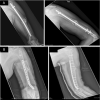

Bone devitalization is believed to be a critical determinant of complications such as infection or nonunion. However, intraoperative assessment of bone devitalization, particularly in open fractures and infections, remains highly subjective resulting in variation in treatment. Optical imaging tools, particularly dynamic contrast-enhanced fluorescence imaging, can provide real-time, intraoperative assessment of bone and soft tissue perfusion, which informs the tissues' ability to heal and fight infection. We describe a novel technique to apply indocyanine green-based fluorescence imaging, using a device that is frequently used in the operating room to assess skin or flap perfusion in plastic surgery, to assess bone and deep tissue perfusion in three pertinent cases: (1) a chronic infection/nonunion after a Gustilo type 3A tibia fracture (patient 1), (2) an acute Gustilo type 3C tibia open fracture with extensive degloving/soft tissue stripping (patient 2), and (3) an atrophic nonunion of the humerus (patient 3). In all three cases, fluorescence imaging (both time-specific fluorescence and maximum fluorescence) and derived kinetic maps of time-to-peak, ingress slope, and egress slope demonstrated clear spatial variation in perfusion that corresponded to the patient pathogenesis. The impact of this information on patient outcome will need to be evaluated in future clinical trials; however, these cases demonstrate in principle that optical imaging information has the potential to inform surgical practice, reduce the variation in treatment, and improve outcomes observed in these challenging patients.